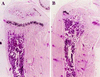

Mice in which the genes encoding the parathyroid hormone (PTH)-related peptide (PTHrP) or the PTH/PTHrP receptor have been ablated by homologous recombination show skeletal dysplasia due to accelerated endochondral bone formation, and die at birth or in utero, respectively. Skeletal abnormalities due to decelerated chondrocyte maturation are observed in transgenic mice where PTHrP expression is targeted to the growth plate, and in patients with Jansen metaphyseal chondrodysplasia, a rare genetic disorder caused by constitutively active PTH/PTHrP receptors. These and other findings thus indicate that PTHrP and its receptor are essential for chondrocyte differentiation. To further explore the role of the PTH/PTHrP receptor in this process, we generated transgenic mice in which expression of a constitutively active receptor, HKrk-H223R, was targeted to the growth plate by the rat alpha1 (II) collagen promoter. Two major goals were pursued: (i) to investigate how constitutively active PTH/PTHrP receptors affect the program of chondrocyte maturation; and (ii) to determine whether expression of the mutant receptor would correct the severe growth plate abnormalities of PTHrP-ablated mice (PTHrP-/-). The targeted expression of constitutively active PTH/PTHrP receptors led to delayed mineralization, decelerated conversion of proliferative chondrocytes into hypertrophic cells in skeletal segments that are formed by the endochondral process, and prolonged presence of hypertrophic chondrocytes with delay of vascular invasion. Furthermore, it corrected at birth the growth plate abnormalities of PTHrP-/- mice and allowed their prolonged survival. "Rescued" animals lacked tooth eruption and showed premature epiphyseal closure, indicating that both processes involve PTHrP. These findings suggest that rescued PTHrP-/- mice may gain considerable importance for studying the diverse, possibly tissue-specific role(s) of PTHrP in postnatal development.